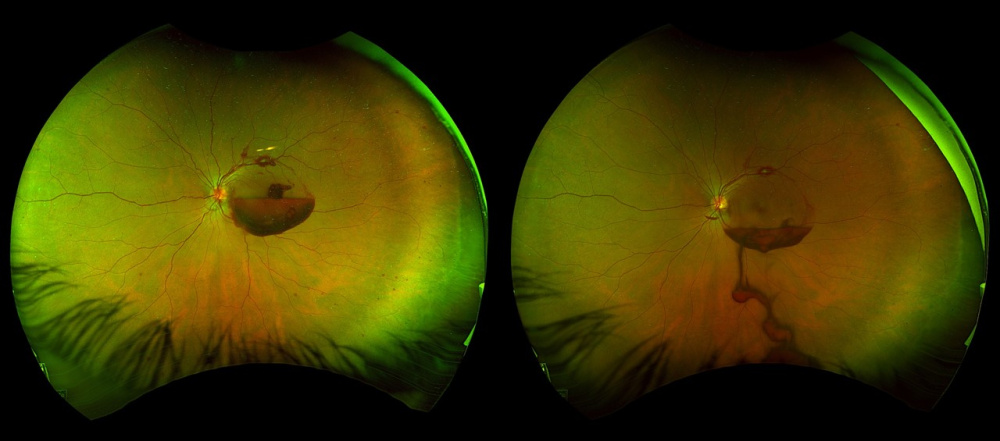

Título: Premacular hemorrhage before and after Nd:YAG laser posterior hyaloidotomy

Descrição: Ultra-widefield fundus photographs demonstrating a premacular hemorrhage before (left) and after (right) Nd:YAG laser posterior hyaloidotomy.